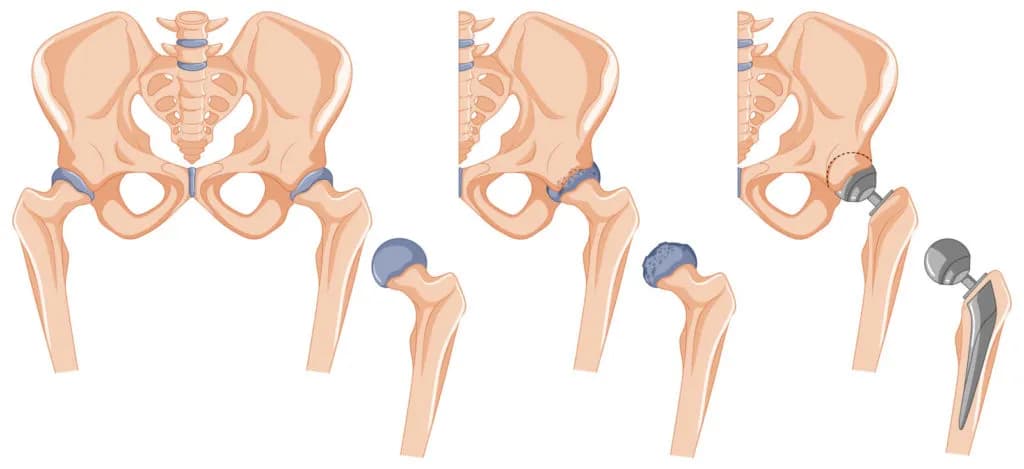

Obluzowanie endoprotezy stawu biodrowego to poważny problem, który może prowadzić do wielu nieprzyjemnych objawów. Pacjenci, którzy doświadczają tego stanu, mogą odczuwać narastający ból, ograniczenie ruchomości oraz inne dolegliwości, które powinny skłonić ich do konsultacji lekarskiej. Wczesne rozpoznanie objawów obluzowania protezy jest kluczowe dla skutecznego leczenia i uniknięcia poważniejszych komplikacji.

W artykule omówimy najczęstsze objawy związane z obluzowaniem endoprotezy stawu biodrowego, różnice między obluzowaniem aseptycznym a septycznym, a także wskazówki dotyczące momentu, w którym warto skonsultować się z lekarzem. Wiedza na ten temat może pomóc w szybszym podjęciu odpowiednich działań i poprawie jakości życia pacjentów.

Diagnostyka obluzowania endoprotezy stawu biodrowego jest kluczowa dla oceny stanu zdrowia pacjenta i podjęcia odpowiednich działań. W pierwszej kolejności lekarz może zlecić badania obrazowe, takie jak rentgen, które pomagają w ocenie stanu protezy oraz otaczających struktur. W przypadku podejrzenia obluzowania, rezonans magnetyczny (MRI) może dostarczyć bardziej szczegółowych informacji na temat tkanek miękkich i ewentualnych uszkodzeń. Dodatkowo, wykonanie tomografii komputerowej (CT) może być pomocne w ocenie przemieszczenia implantu lub zmian w strukturze kostnej. W niektórych przypadkach lekarz może również zlecić badania laboratoryjne, aby ocenić ogólny stan zdrowia pacjenta oraz wykluczyć infekcje, które mogą wpływać na stan endoprotezy.